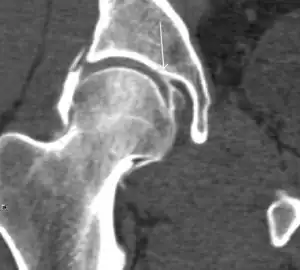

Figure 7:

-

Axial CT image of pigmented villonodular synovitis eroding the posterior cortex of the femoral neck.[1] -

Sagittal T2* gradient echo image showing a posterior soft tissue mass with hypointense areas secondary to hemosiderin deposition.[1] -

X-ray of synovial chondromatosis.[1] -

CT of synovial chondromatosis.[1]